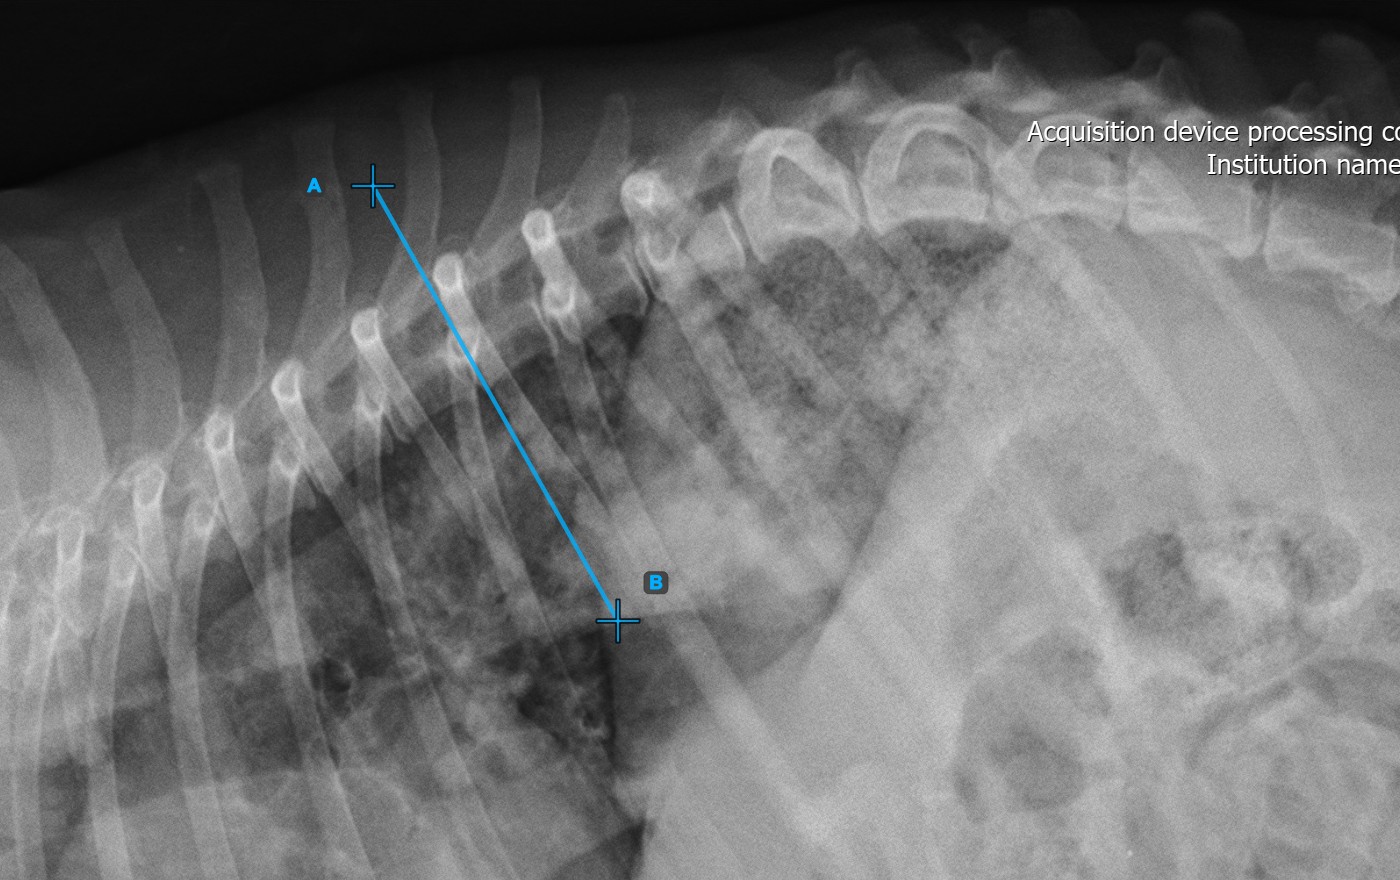

Beginnen Sie die Messung, indem Sie die erste Wirbellinie an der Wirbelsäule markieren.

Identifizieren Sie die Wirbelendplatte am Anfangspunkt der größten Wirbelsäulenkrümmung. Platzieren Sie den Start- und Endpunkt der ersten Wirbellinie genau entlang der identifizierten Endplatte. Passen Sie bei Bedarf jeden Punkt in der Szene an, um die Linie besser an die Endplatte auszurichten.

Das Bild unten zeigt eine typische Platzierung der ersten Wirbellinie.